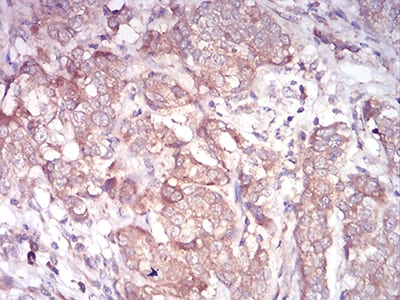

Immunohistochemical analysis of paraffin-embedded human bladder cancer tissues using ARF1 mouse mAb with DAB staining.

Immunohistochemical analysis of paraffin-embedded human stomach cancer tissues using ARF1 mouse mAb with DAB staining.